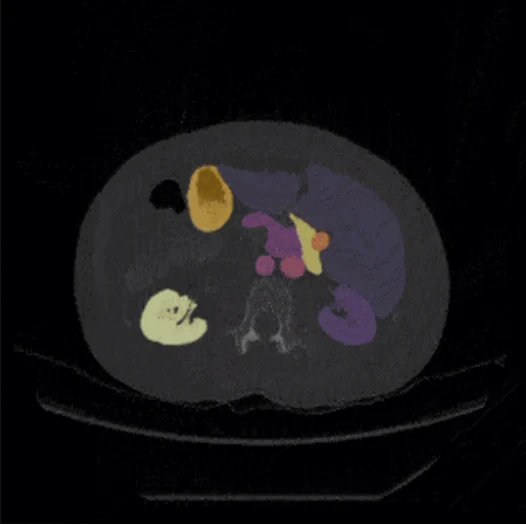

Pareidolia’s annotation of medical images spans diverse pathologies — from coronary artery calcification and obstructive hydrocephalus to complex multi-organ segmentation tasks — precisely to ensure this clinical breadth in every dataset delivered.

Pixel-accurate segmentation across CT, MRI, PET, ultrasound, X-ray, and digital pathology. Domain-driven annotation workflows covering organ, lesion, vessel, and disease pathology segmentation with multi-layered quality assurance in medical imaging. AI-ready output formats suitable for all major machine learning frameworks.

Comprehensive medical image labeling services — bounding boxes, polygons, keypoints, semantic masks, measurement tasks, and complex multi-class annotations. Expert annotation spanning coronary artery calcification, obstructive hydrocephalus, and hundreds of other disease patterns. Multi-modal support across X-ray, CT, MRI, ultrasound, and digital pathology.